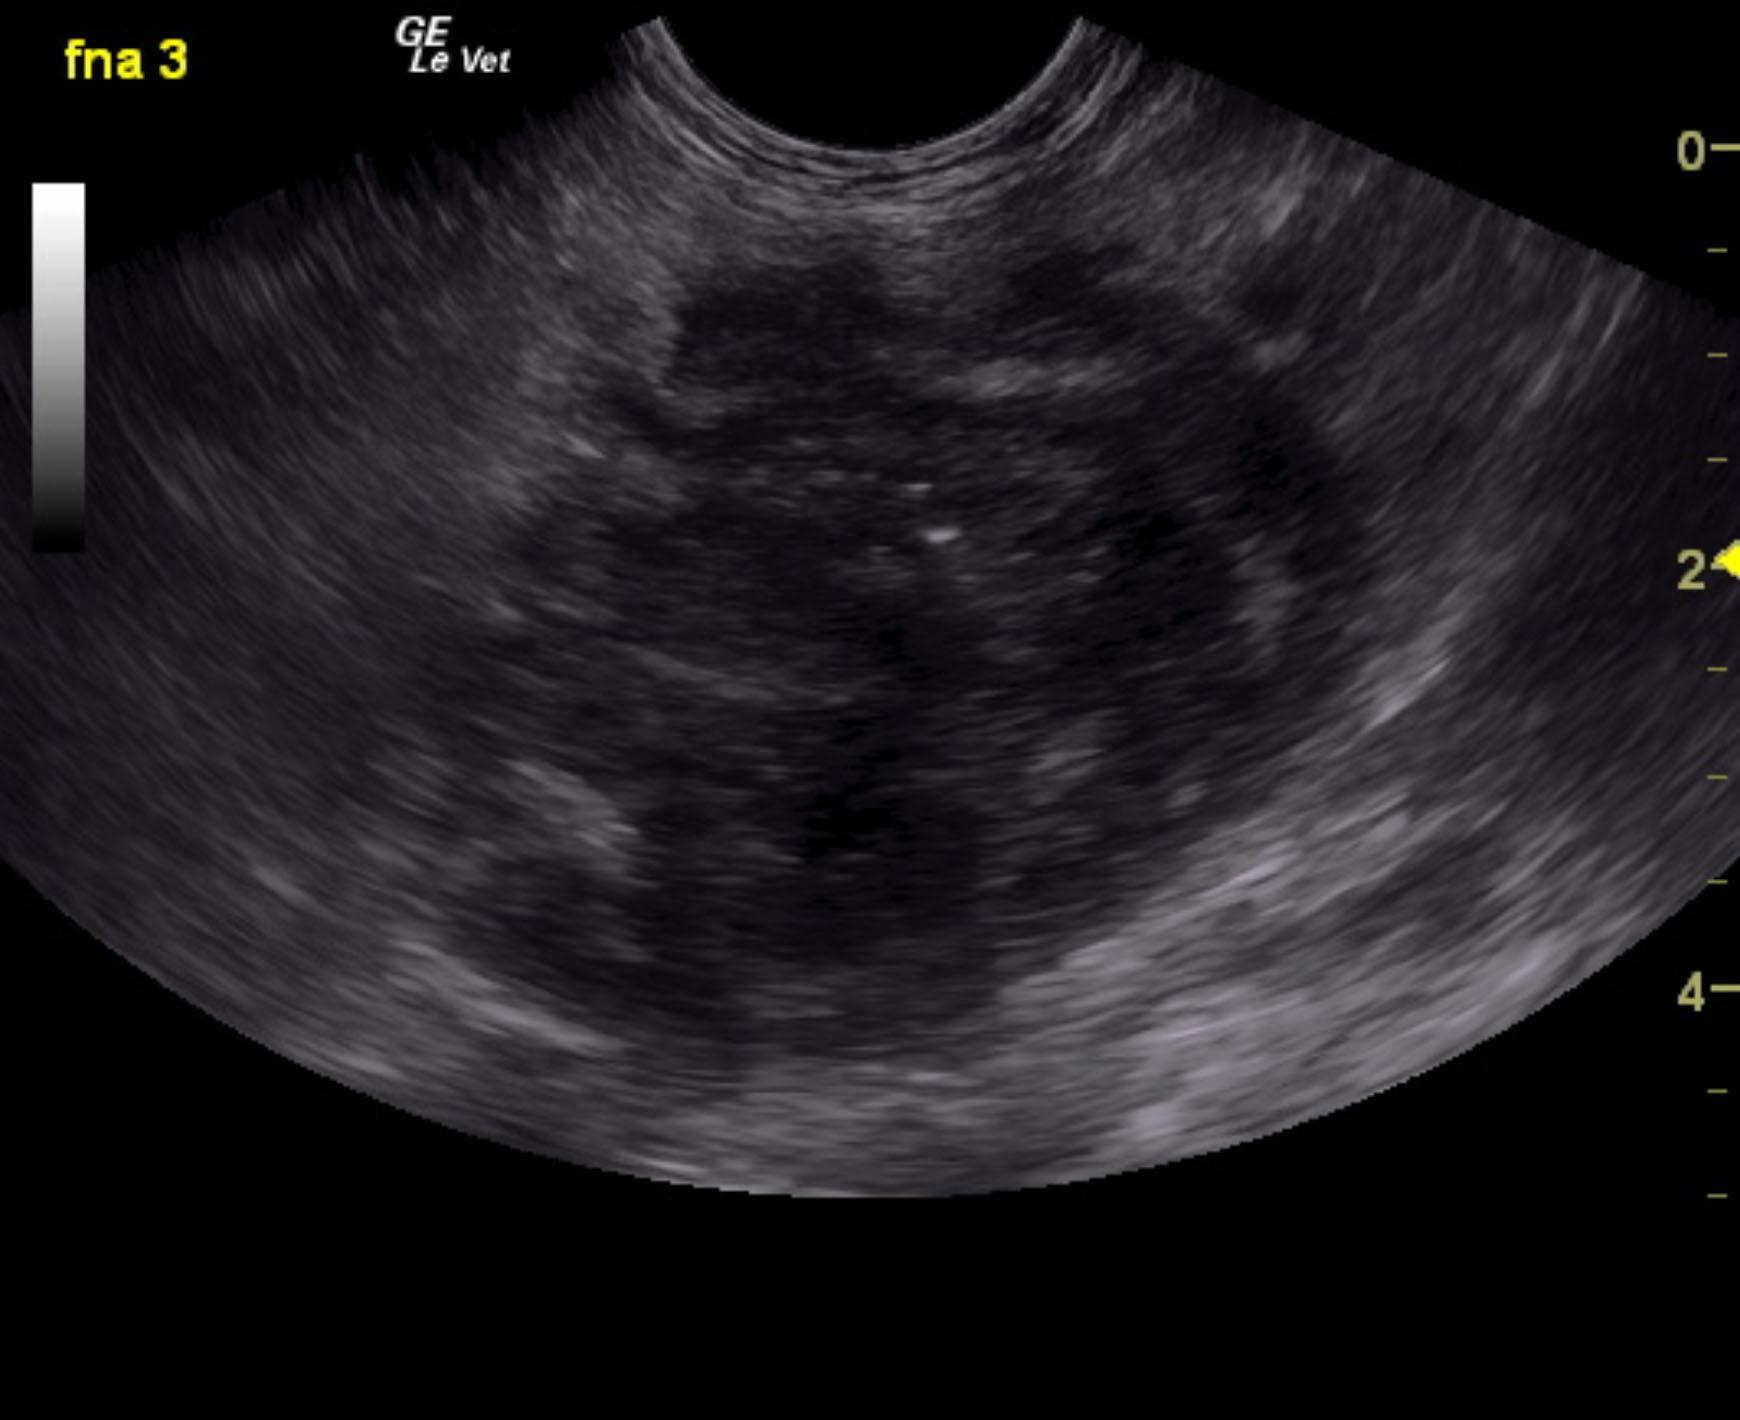

A 16-year-old SF DSH with a history of diabetes and hyperthyroidism was presented for evaluation of vomiting, diarrhea, and anorexia. Urinalysis showed SG of 1.017, proteinuria, and hematuria with negative bacterial growth. Coagulation panel was mildly elevated.

A 16-year-old SF DSH with a history of diabetes and hyperthyroidism was presented for evaluation of vomiting, diarrhea, and anorexia. Urinalysis showed SG of 1.017, proteinuria, and hematuria with negative bacterial growth. Coagulation panel was mildly elevated.